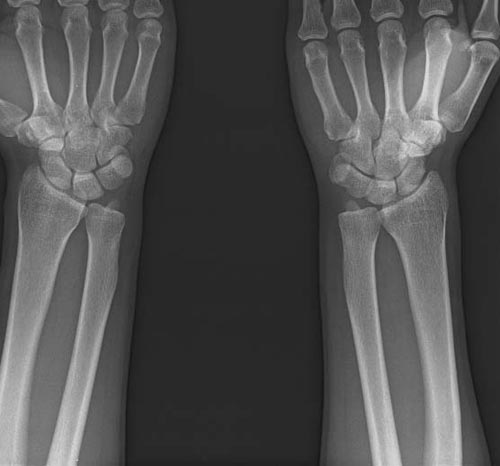

x线检查月前片示双踝关节骨质未见明显异常。一月后肿胀大部消失,疼痛稍有好转,摄片示两侧骨下段条带状高密度影,边界尚清。ct扫描示两侧胫骨下段骨皮质增厚不明显,髓腔内密度显示磨玻璃样增高,髓腔显示狭窄。

x线检查一个月前示双踝关节骨质未见异常。一个月后肿胀大部消失,疼痛稍有好转,摄片示两侧胫骨下段横行条状高密度影,边界较清。ct扫描示:两侧胫骨下段未见骨皮质增厚,两胫骨下段近骨端处可见骨小梁增粗但纹理尚清晰,未见明显骨质破坏,邻近关节及关节囊未见明显异常,软组织内未见异常.综上所诉考虑1.低毒感染所致,2.假性痛风

x线片表现为双侧胫骨下端粗条状磨玻璃样增高密度影,并可见骨皮质稍不连续。ct表现为双侧胫骨下端髓腔内磨玻璃样增高密度影,未见明显骨皮质不连续(可能与扫描体位有关)。

本例应该考虑为双侧胫骨下端应力性骨折。

现在看来,该患者确实是疲劳性骨折,这几个月来已经差不多好了,线状影也基本消失了,下次发图片给各位战友看。但是很纳闷他工作轻松,又没有什么剧烈运动。